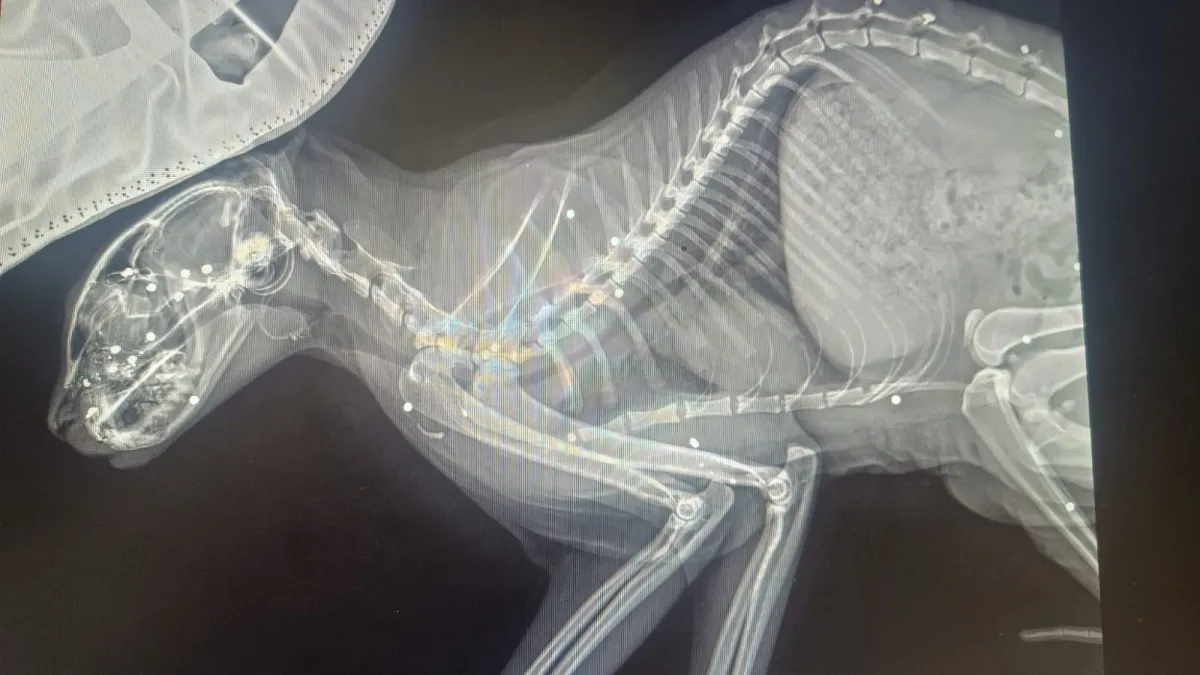

Leo era abituato a trascorrere le giornate all’aperto, rientrando regolarmente ogni sera. Lo scorso 16 ottobre, però, il gatto non è tornato a casa e la famiglia, preoccupata, lo ha cercato senza sosta. Undici giorni più tardi, il felino è stato ritrovato davanti alla porta di casa in condizioni drammatiche: "ridotto a pelle e ossa, coperto di fango e sangue e con il muso pieno di buchi", raccontano i familiari.Il gatto è stato immediatamente trasportato dalla dottoressa Beatrice Borrani, veterinaria a Città di Castello, che ha riscontrato ferite gravissime. Le radiografie hanno evidenziato numerosi pallini di piombo conficcati nel cranio e nel corpo, indizio, secondo la professionista, di "un colpo ravvicinato e intenzionale, non un incidente occasionale"

Le conseguenze per Leo sono particolarmente gravi: ha perso completamente la vista da un occhio, mentre nell’altro permane solo una flebile possibilità di recupero, subordinata all’evoluzione dell’edema cerebrale. Il gatto è attualmente sottoposto a cure intensive e a un monitoraggio continuo, con prognosi riservata.

Leo resta sotto stretto controllo veterinario a causa della gravità delle lesioni. Le radiografie hanno evidenziato numerosi corpi estranei nel cranio, condizione che complica il decorso clinico e aumenta il rischio di danni neurologici permanenti. Le terapie in corso prevedono il trattamento dell’edema cerebrale, medicazioni mirate e un monitoraggio continuo delle funzioni vitali e neurologiche.

I proprietari hanno organizzato turni di assistenza h24 per garantire al gatto le migliori cure possibili, somministrando i farmaci prescritti e verificando quotidianamente l’evoluzione dello stato clinico. Nonostante la gravità, permane una flebile possibilità di recupero parziale della vista da un occhio, subordinata all’andamento dell’edema e alla risposta alle terapie; la prognosi resta comunque riservata.